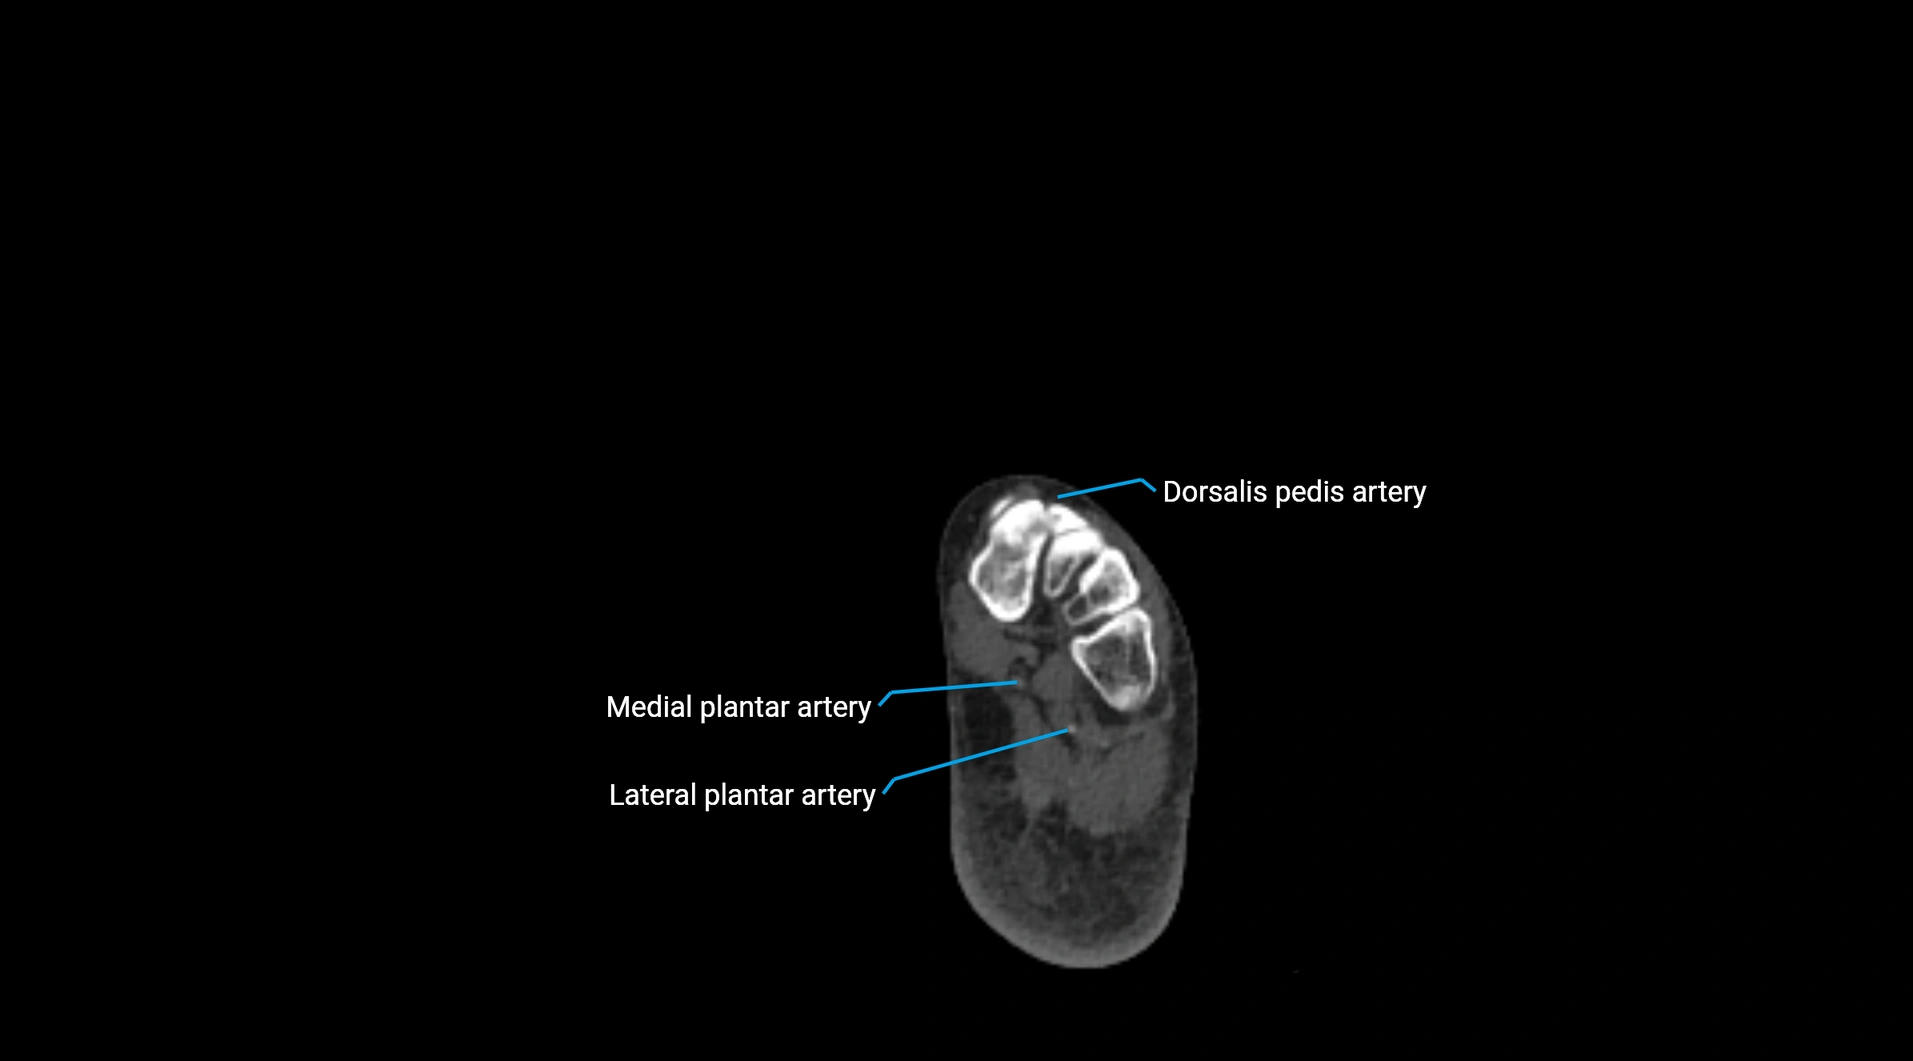

CT images

image